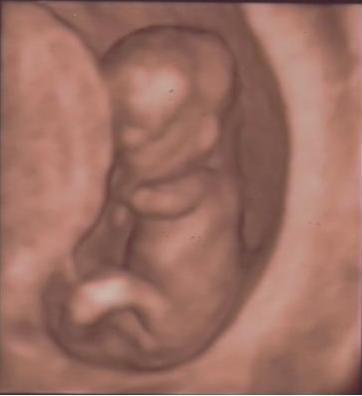

Mi az Istenhegyi Géndiagnosztikai-ban voltunk, és nagyon meg voltam elégedve velük, az ember csak ámul, hogy ma már micsoda technikák vannak ... Egy hatalmas tévén nézhettem, ahogy produkálja magát a drágaság, és mivel elég nehezen akart abba a pozícióba fordulni, hogy a doki meg tudja mérni, így kb. 10 percig gyönyörködhettünk benne. A doki nagyon jó fej volt, közben kommentálta a dolgokat

De a kis huncut a lába közét nem mutatta meg, így a neme egyelőre titokban maradt, bár a férjem mondta, hogy ő nagyon igyekezett kifigyelni, de hiába. És tényleg tök jó, hogy utána DVD-n megkaptuk az egészet.